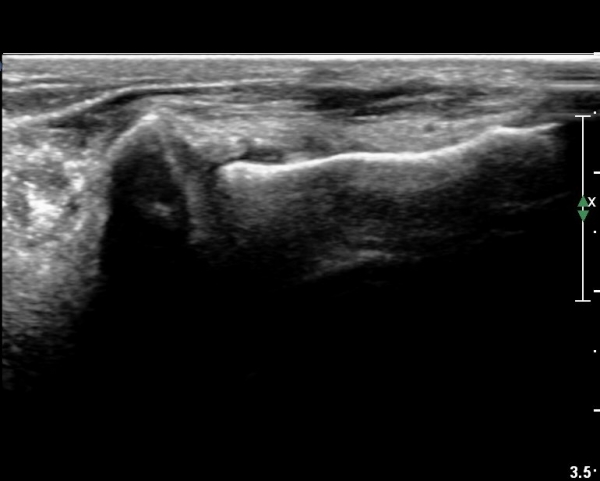

¸»´Ü °æ°ñºñ°ñÀδëÀÇ ÆÄ¿­ÀÌ °üÂûµÇ°í(»çÁø 4, 5)

ºÎÇÏ°Ë»ç ½Ã °æ°ñ°ú ºñ°ñÀÌ ¹ú¾îÁö°í ¼ö¾×ÀÇ À̵¿ÀÌ °üÂûµÈ´Ù(÷ºÎµ¿¿µ»ó 1)